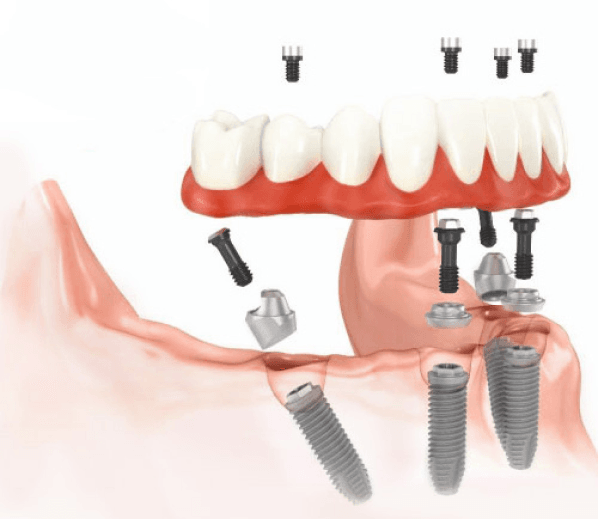

В большинстве случаев всё, что потребуется пациенту, это установка только шести имплантов. Это даст стоматологу возможность поставить несъёмный протез. В таком случае пациент будет чувствовать себя совершенно комфортно — его искусственные зубы будут так же функциональны, как и родные.

Помимо этого, возможна имплантация по другой методике. Используя её, можно поставить несъёмные зубные протезы даже на челюсть, на которой полностью удалены или утрачены зубы. При этом всё, что потребуется сделать, это установить четыре искусственных зуба.